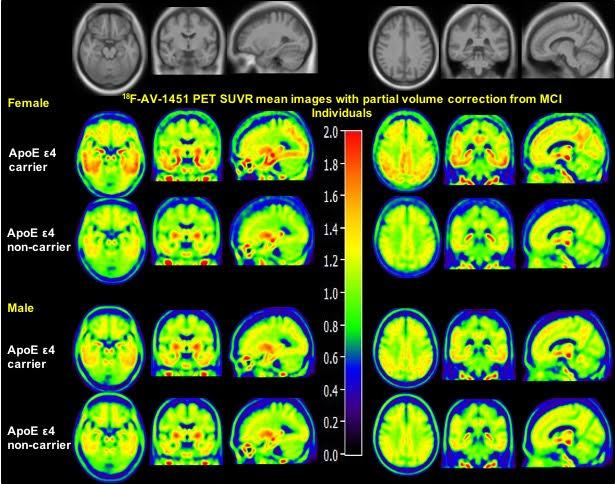

image: Sex Modulates the ApoE ε4 Effect on 18F-AV-1451 Tau PET.

The strongest genetic risk factor for Alzheimer's disease is the apolipoprotein E type 4 allele (ApoE ε4). Research presented by Manish Paranjpe at the 2019 Annual Meeting of the Society of Nuclear Medicine and Molecular Imaging (SNMMI) used positron emission tomography (PET) to show that women who are ApoE ε4 carriers and already experiencing mild cognitive impairment are more susceptible than men to tau accumulation in the brain.

"Sex plays an important role in Alzheimer's disease risk, with females having a higher lifetime risk of developing the disease and an increased vulnerability to genetic risk factors," points out Yun Zhou, who led the project at the Mallinckrodt Institute of Radiology, Washington University in St. Louis School of Medicine. He explains, "This is the first study to demonstrate that sex modulates the effect of ApoE ε4 on brain tau depositing, measured using 18F-AV-1451-PET imaging, in the entorhinal cortex, amygdala, parahippocampal gyrus, and posterior cingulate of the brains of patients with mild cognitive impairment (MCI). Strikingly, females experience greater ApoE ε4-associated increases in brain tau deposition in these regions compared to their male counterparts."

This cross-sectional study involved 131 cognitively normal (CN) elderly controls (66 women) and 97 MCI subjects (39 women) from the Alzheimer's Disease Neuroimaging Initiative (ADNI) database. The mean age of all was 77. Preprocessed 18F-AV-1451 PET images, T1-weighted structural MRI scans and demographic information were included. After downloading pre-processed images from ADNI, a partial volume correction method was applied on all PET images (improving spatial resolution and contrast), and structural MRIs were used for PET spatial normalization. All statistical analyses were performed after controlling for baseline age and education.

In addition to finding women with the ApoE ε4 mutation more susceptible than men to tau accumulation, Zhou notes: "Our study also confirmed that sex does not modulate the ApoE ε4-associated tau deposition in the brains of cognitively normal elderly individuals, and it extends our understanding of how sex modulates the ApoE ε4 effect on tau deposition in the brains of individuals at the early stage of Alzheimer's disease."